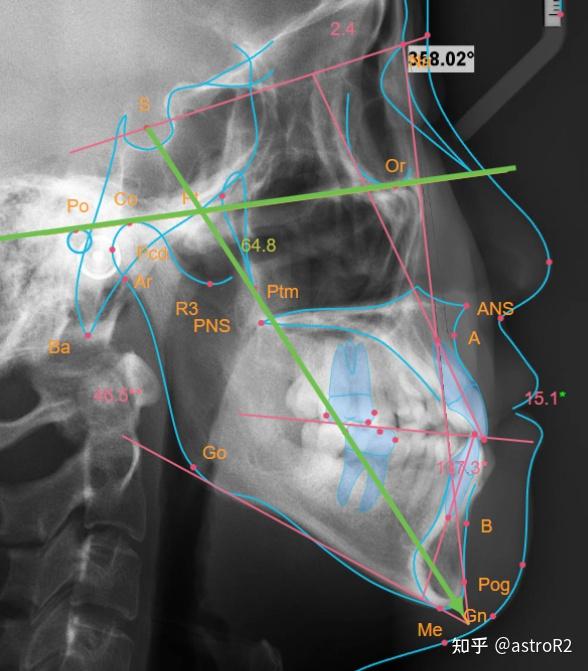

正畸头影测量标准值与项目

深入了解头影测量中的多种角度项目

首先,我们来看看最常见的三个头影测量角度:sna,snb和anb,它们在正畸